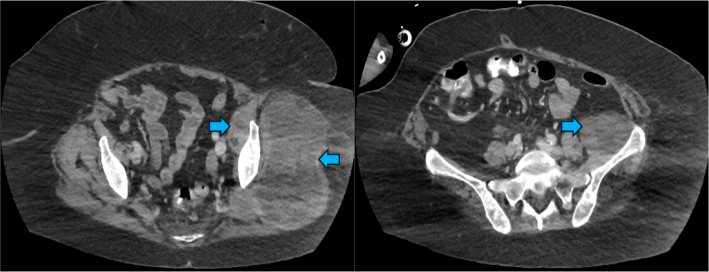

Guillain-Barré syndrome is an immune-mediated neuropathy characterised by acute-onset of symmetric, ascending motor weakness and areflexia. Acute motor axonal neuropathy, a severe axonal variant, is distinguished by direct axonal injury and poor functional recovery. Although infections are recognised triggers for Guillain-Barré syndrome, it is notable that up to half of cases occur without a preceding infectious event, suggesting that other factors such as underlying malignancy may contribute to disease onset. We present a rare and fatal case of acute motor axonal neuropathy in a 70-year-old woman, who was ultimately found to have an underlying pleomorphic liposarcoma. The patient presented with one week of progressive weakness, fatigue and encephalopathy. She required urgent mechanical ventilation due to respiratory failure; imaging identified multiple bilateral pulmonary nodules. Neurologic evaluation confirmed acute motor axonal neuropathy through nerve conduction studies and cerebrospinal fluid analysis, which showed albuminocytologic dissociation and positive anti-GM1 IgG antibodies. Despite standard treatment with intravenous immunoglobulin, the patient experienced no neurological recovery. Further imaging revealed a large pelvic mass, that was not present on a scan performed two months earlier. A biopsy confirmed pleomorphic liposarcoma, a rare and aggressive soft tissue sarcoma. Paraneoplastic panel testing was negative for onconeural antibodies, yet the clinical context raised suspicion for an immune-mediated, tumour-associated neuropathy. Clinicians should maintain a high level of suspicion of underlying malignancy in patients with Guillain-Barré syndrome, especially in the absence of preceding infection and with rapid neurological decline.